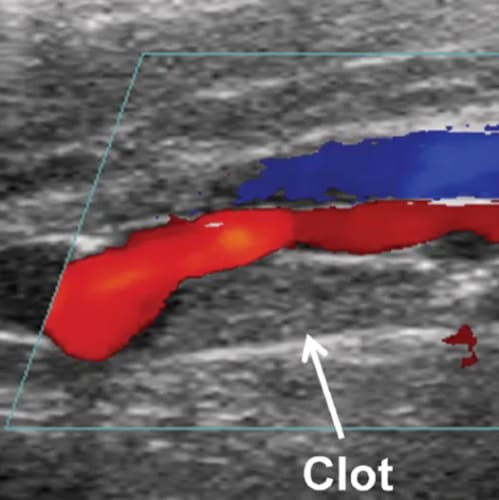

What is a DVT Doppler Ultrasound?

A Deep Vein Thrombosis (DVT) Doppler Ultrasound is a special type of ultrasound which is used to measure blood flow through the upper limb veins as well as the deep leg veins and assess any blockage to blood flow such as a blood clot. DVT commonly occurs in calf veins, and occasionally in those of the thigh.

When isolated in the leg veins, DVT can result in pain, skin inflammation and ulceration. However, if the clot breaks off and travels through the bloodstream into the lungs, it is known as pulmonary embolus which can be life-threatening.